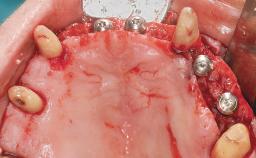

Immediate Loading of Eight Implants in the Maxilla and Six Implants in the Mandible and Final Restoration with Three-Unit and Four-Unit FDPs

Extensive scientific evidence has confirmed that immediately loaded implants with fixed full-arch provisional restorations can osseointegrate with success rates similar to conventionally or delayed loaded implants. A number of immediate-provisionalization techniques for edentulous jaws have been described. Some protocols differ when it comes to prefabricated provisional templates versus complete denture conversion; intrasurgical impressions versus direct relining; and cemented versus screw-retained provisional restorations. In this context, complete-denture conversion has been proposed for either intrasurgical impressions or direct relining. Another possibility is the utilization of a prefabricated provisional to be adapted either in the mouth (by direct relining) or in the laboratory (on a working model obtained from an intrasurgical impression).

Loading Protocol Immediate

Provisional Implant-Supported Prosthesis Prosthodontic margin < 3 mm apical to mucosal crest Prosthodontic margin < 3 mm apical to mucosal crest